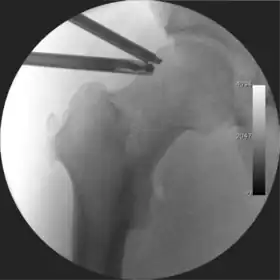

![]() Intraoperative fluoroscopic image during an arthroscopic resection of a cam lesion of the femur. The upper instrument is the arthroscope (viewing device), while the lower is the high-speed burr used for reshaping the bone. |

Figure 4. A needle is passed into the joint, breaking the 'suction seal', and allowing further distraction of the hip joint with minimal extra traction

The next step is to insert a fine needle under x-ray guidance into the hip joint. This breaks the 'suction seal' of the joint and allows further distraction if necessary (see fig 4). The surgeon wishes to see the ball move out the socket by approximately 1 cm, so that access to the hip joint can be achieved with minimal risk of damage to the joint surfaces. Most surgeons will inject fluid into the joint at this stage, again to ensure that there is enough space between the ball and socket for safe instrument access. This needle is then removed. The next step is placement of the 'portals', or the small holes made to pass instruments into the joint. This is achieved by again passing a fresh hollow needle into the joint under x-ray control, usually in a slightly different position. The reason for this is so the surgeon can ensure that the needle, and subsequent cannulae do not penetrate and damage the acetabular labrum or cartilage joint surfaces (see fig. 5). Again, surgeons will have their own preferences as to their preferred placement. Through this hollow needle, a long thin flexible guide wire is passed into the joint, and the needle is removed over it, leaving the guide wire in situ. A small cut in the skin is made around the wire, to allow for larger cannulae to be placed over the wire through the portal. The wire therefore guides the larger cannulae into the joint. The most common external diameters of cannulae used are between 4.5 and 5.5 mm. Once the surgeon is satisfied that the cannula is in the correct position, by a combination of feel and x-ray guidance, the guide wire can be withdrawn. Once the first portal is correctly placed, any further portals may be created once the camera is in position, to ensure that they are placed with minimal risk to the joint surfaces. This process can be repeated to gain as many points of entry to the hip joint as the surgeon requires, normally between two and four. Certain of these entry points will be used for the viewing arthroscope and others for operating instruments.

Standard arthroscopic treatment of symptomatic cam FAI involves debridement (resection) or repair of any labral [10] and chondral injuries [11] in the central compartment of the hip, and subsequent reshaping of the head-neck junction of the upper femur (osteochondroplasty) in the peripheral compartment [12][13] using high-speed motorised burrs that are similar in design to a dentist's drill (see fig. 9).